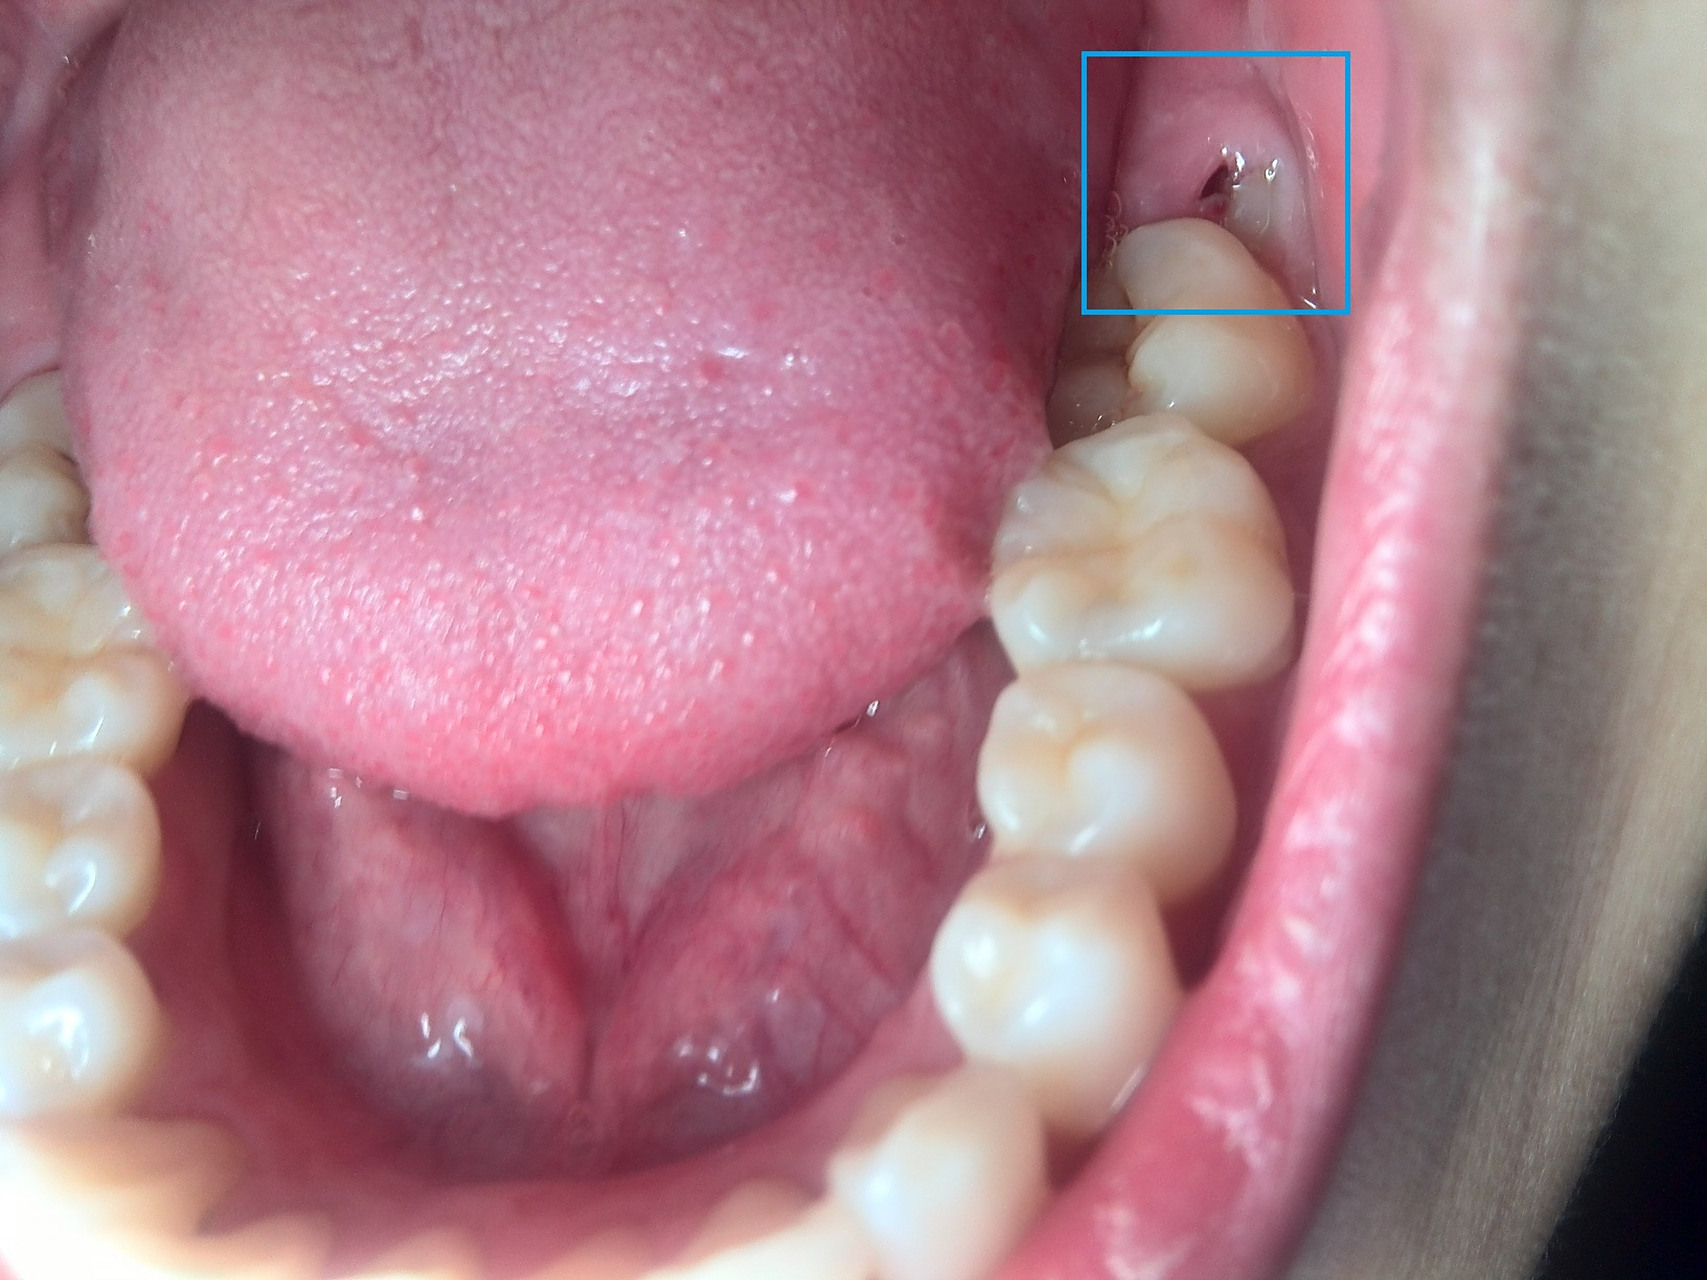

智齿牙后面长了一小块肉,这是怎么回事啊?

图片尺寸3072x4096